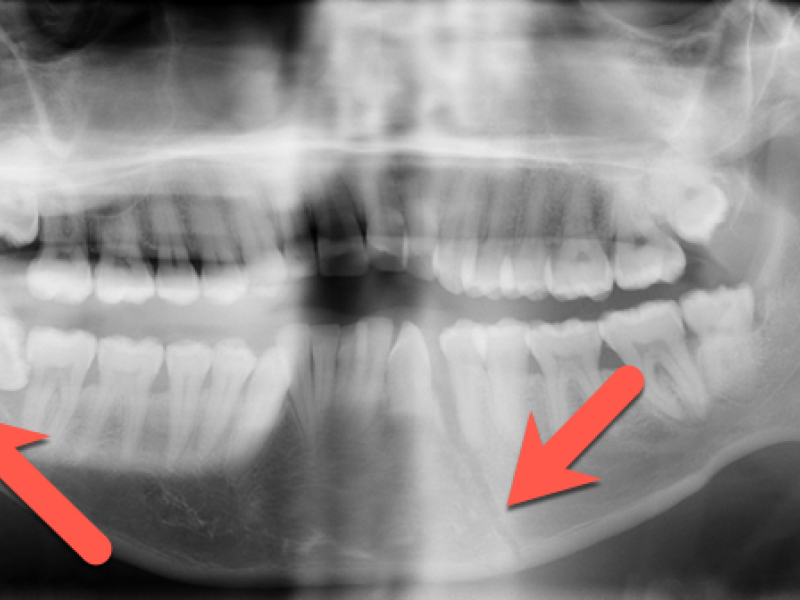

Answer: Mandibular fracture.....but did you see both? (see